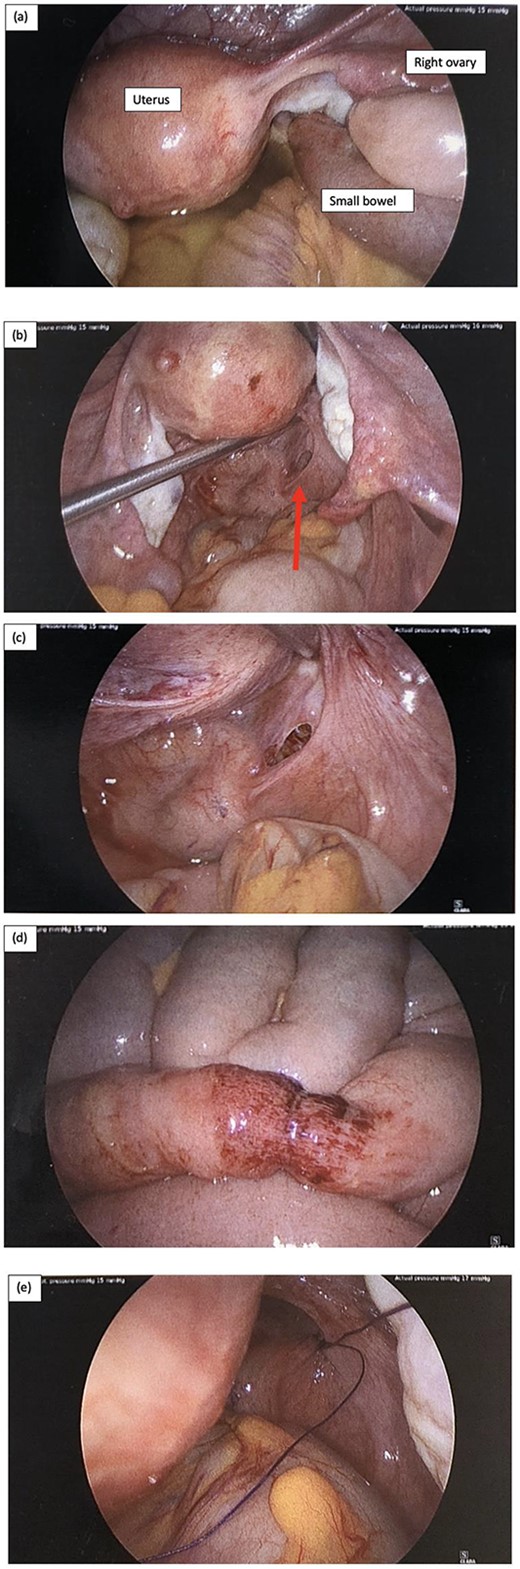

Intraoperative laparoscopy findings, and (a) key landmarks including the uterus and right ovary are identified, as well as a short segment of small bowel diving deep into the pelvis, and there is also moderate volume of serous free fluid; (b) serous fluid has been suctioned and there is small bowel herniating through a small peritoneal defect adjacent to the rectum on the right represented by the red arrow; (c) peritoneal defect in the POD; (d) the short segment of small bowel that was involved incarcerated in the hernia has a small area of bruising but is otherwise viable, and (e) the peritoneal defect was repaired with a single figure of 8 stich using 0 PDS suture.

There was a finding of a nubbin of small bowel herniating through a small peritoneal defect at the peritoneal reflection adjacent to the rectum on the right and moderate serous free fluid was identified (Fig. 2a–c). The small bowel was reduced easily with gentle traction using laparoscopy instruments and a single figure of 8 repair using 0 PDS suture was used to close the peritoneal defect (Fig. 2e). The short segment of small bowel which was incarcerated within the hernia was bruised as shown in Fig. 2d but viable. The small bowel was examined from duodenum to the terminal ileum and no other injuries were identified. The appendix was also mildly injected and removed laparoscopically. Patient was allowed sips of clear fluid postoperatively and NGT continued on free drainage and 4-hourly manual aspirations.